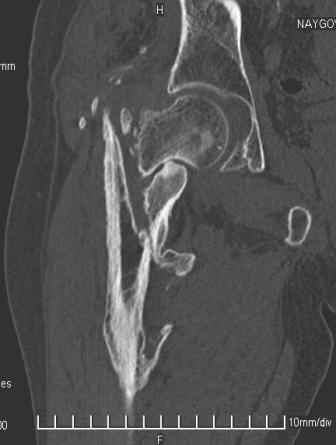

Сросшийся со смещением чрез-подвертельный перелом

Больной Н. 44 года травма 1,5 года назад июнь 2008 года чрез-под вертельный перелом правого бедра. Во время лечения у больного развился алк. делирий, проводилось консервативное лечение перелома.

Осмотрен 30.10.09.

Беспокоят боли, укорочение конечности. Укорочение 3 см. Ногу поднимает, сгибание ограничено, ротационные движения в полном объеме. На КТ перелом сросся за счет костной мозоли. Что делать?

Протез? Если «да» Можно ли обойтись стандартной ножкой Corail?

Или межвертельная остеотомия?